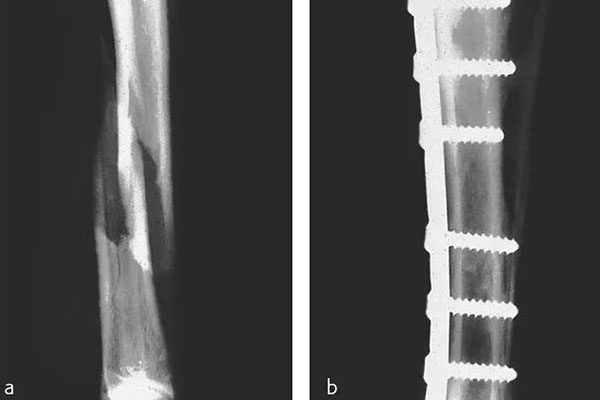

那在檢測(cè)的時(shí)候還需要看到植入物的情況,但由CFPEEK復(fù)合材料制成的零件通常具有放射透性,幾乎無(wú)法通過(guò)X射線檢測(cè)。就通過(guò)添加諸如鉭絲之類的X射線散射材料,可以使植入物變得可見(jiàn)??梢钥聪聢D展示了一個(gè)固定骨折骨頭的骨愈合板??梢钥闯觯ㄟ^(guò)設(shè)計(jì)已對(duì)放射密度進(jìn)行了定制,以便在盡量減少對(duì)骨折部位遮擋的同時(shí)可視化組件。重要的是,實(shí)現(xiàn)X射線可見(jiàn)性的同時(shí)也能保持清晰的MRI圖像。